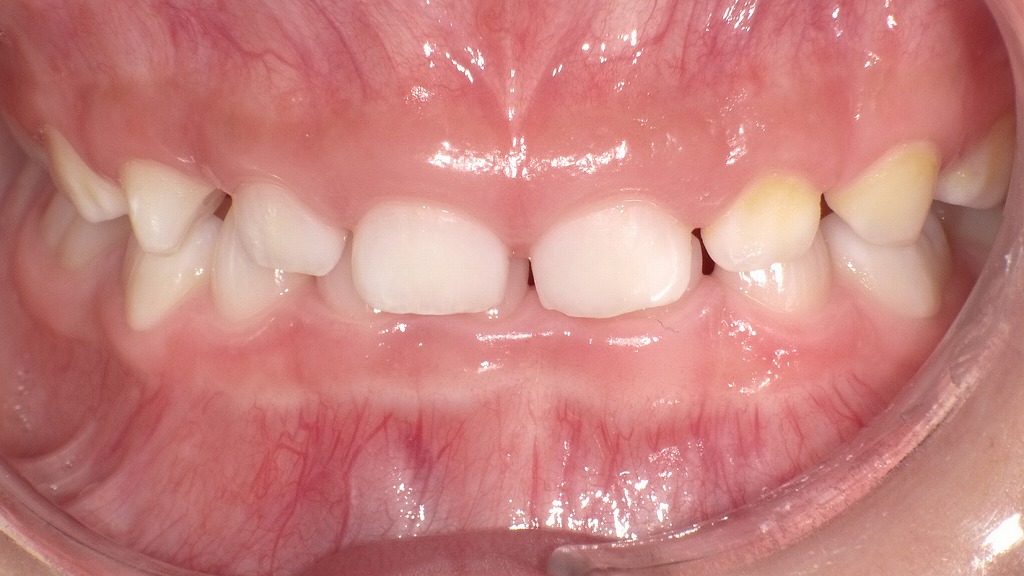

症例1:子ども(乳歯)の過蓋咬合

この写真は、子どもの口腔内(乳歯列期)の「過蓋咬合(かがいこうごう)」を示しています。

過蓋咬合とは、上の前歯が下の前歯を過剰に覆っている状態を指します。正常な咬み合わせでは、上の前歯が下の前歯を2〜3mm程度覆うのが理想ですが、この写真では上の前歯が下の歯を深く覆い隠しており、下の歯の見える部分が少ないのが特徴です。

👧 子ども(乳歯期)に見られる特徴

- 成長過程で下顎の発育がやや遅れていることが多く、上顎が前方に出て見える。

- 下の前歯が上の前歯の裏側に深く入り込み、咬み合わせが深い(ディープバイト)。

- 放置すると、下の歯の歯ぐきや上顎前歯の裏側が傷つく場合がある。